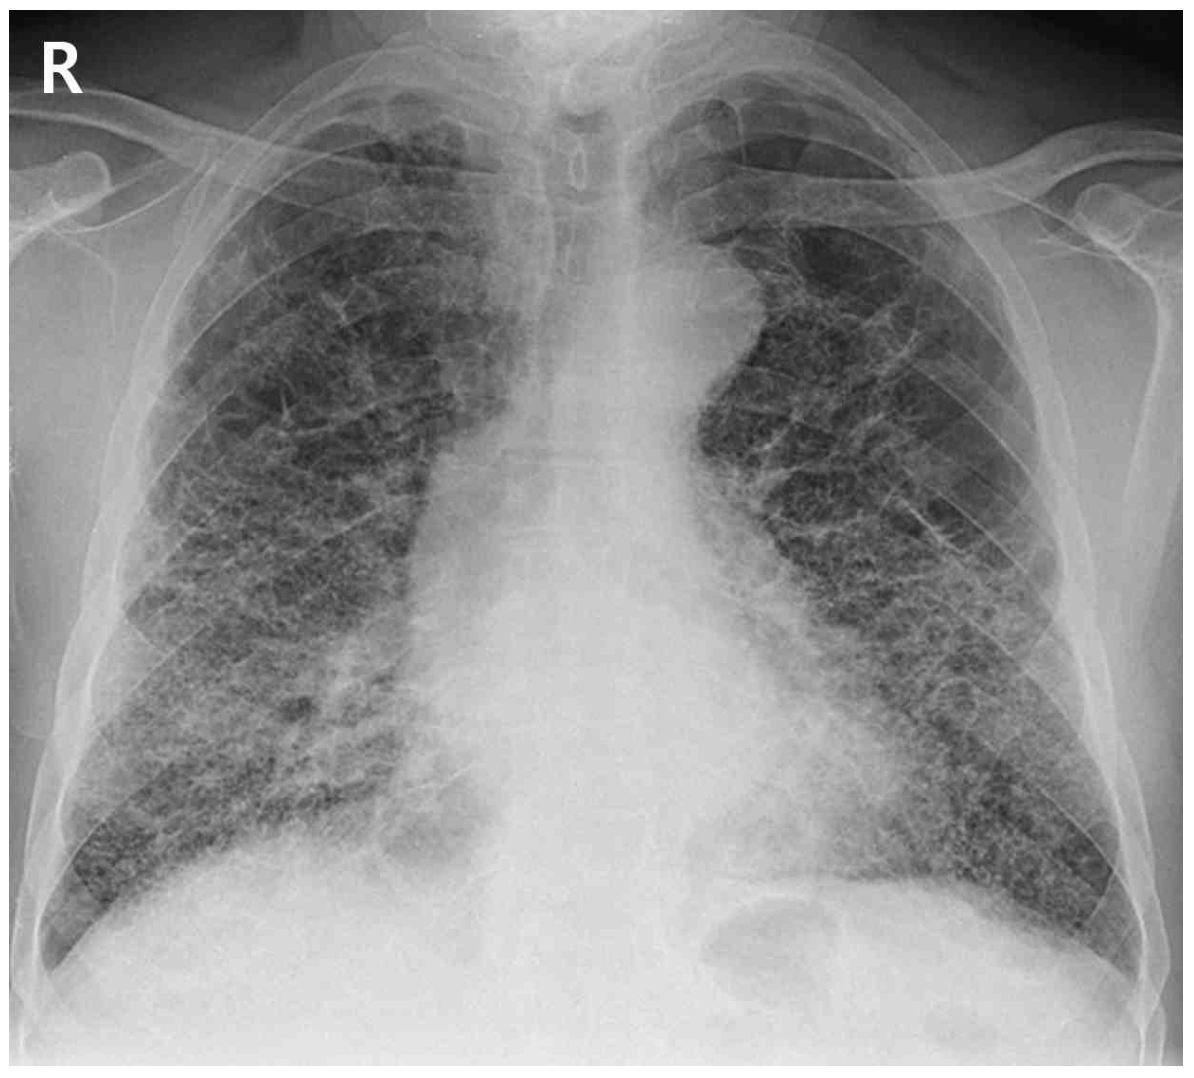

58세 남자가 1개월 전부터 숨이 더 찬다며 병원에 왔다. 6년 전 특발폐섬유증으로 진단되어 항섬유화제를 복용 중이다. 호흡곤란은 최근 3년간 점차 진행하여 최근에는 가만히 있을 때도 숨이 차서 집에서 코삽입관 산소 3 L/분 투여 중이다. 30갑•년의 과거 흡연자이다. 혈압 124/86 mmHg, 맥박 118회/분, 호흡 28회/분, 체온 36.6°C이다. 양쪽 가슴에서 거품소리가 들리고 양쪽 곤봉손가락이 관찰된다. 가슴 X선사진과 가슴 컴퓨터단층촬영 사진이다. 검사 결과는 다음과 같다. 고려할 수 있는 치료는?

CXR: Increased reticular markings

• CXR상 폐 전반에 reticular marking이 증가되어 있으며 자세한 평가를 위해 시행한 HRCT에서 subpleural/basal predominance, honeycombing, reticular abnormality의 통상성 간질성 폐렴(UIP) pattern이 관찰되고 있다. 이는 IPF에서 전형적으로 나타나는 영상학적 소견으로, 환자의 악화된 호흡곤란은 새로운 원인보다는 기존에 진단받은 IPF가 진행함에 따라 발생한 것으로 판단된다.